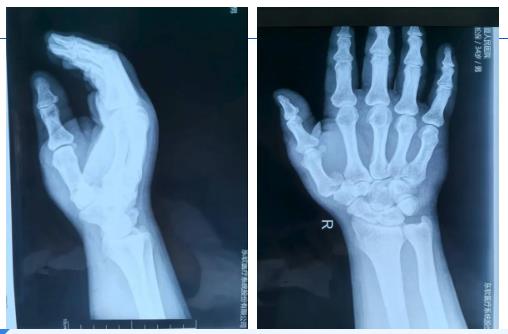

患者因意外摔伤致右手拇指疼痛、活动受限,确诊为右手第一掌骨基底部骨折伴脱位(Bennet骨折)。该类型损伤解剖关系复杂,若处理不当易引发手部功能障碍。目前患者右手已受伤15天,但患处仍轻度肿胀,且活动受限。称多县人民医院外科医生虽具备一定的理论基础,但实操经验不足,此例手术成为精准带教的重要契机。

术前,青南支医骨科医生王登峰结合影像学资料,向称多县人民医院外科团队详解骨折解剖特点、损伤机制及手术关键节点,共同制定手术方案:第一掌骨脱位手法复位+骨折切开复位克氏针内固定+石膏外固定术,特别强调手法复位需精准把控力度与角度,避免二次损伤。